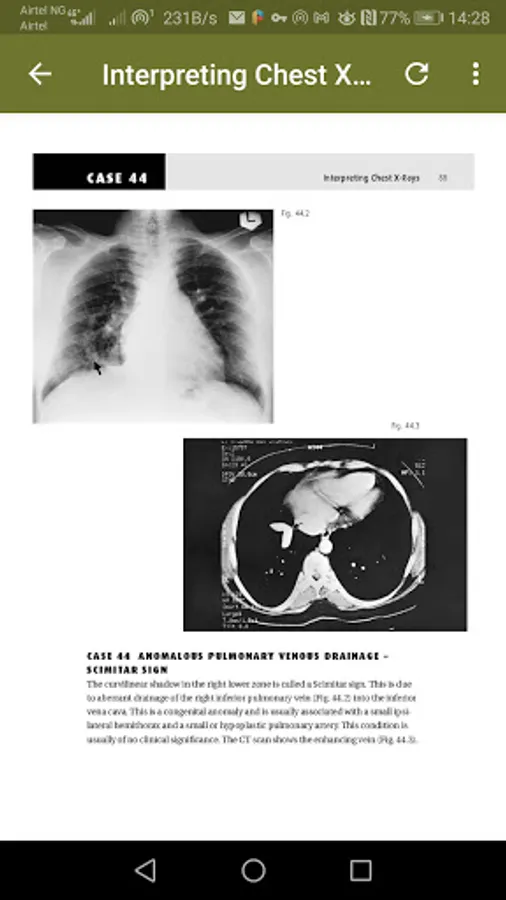

The chest radiography is a very commonly requested examination and it is probably the hardest plain film to interpret correctly. It is, however, often performed out of hours with interpretation undertaken by relatively junior members of staff, frequently with no senior radio-logical advice available. All the X-rays are accompanied by a simple line diagram outlining where the abnormality is.